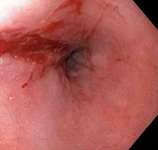

Mallory-Weiss tear

Mallory-Weiss tear after epinephrine injection (the bleeding has stopped, allowing better visualization of the lesion)

From the collection of Juan Carlos Munoz, MD, University of Florida